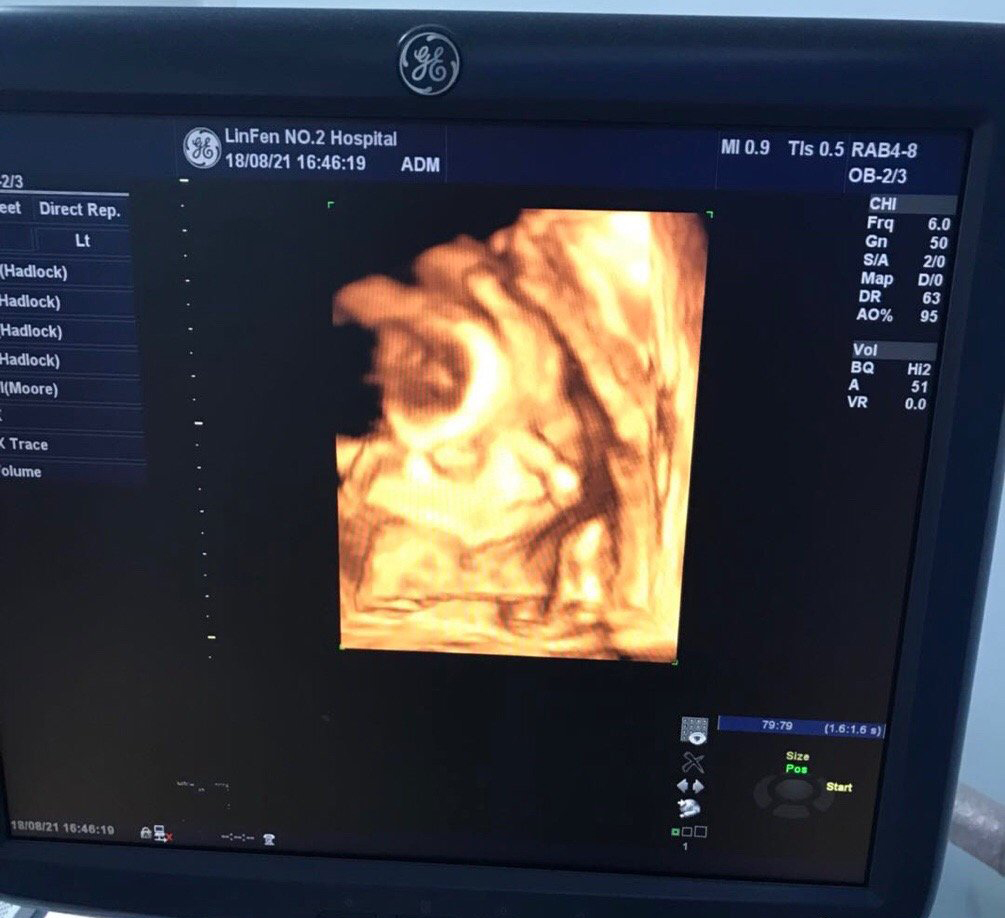

很快我的小外甥二毛一周岁了,参加完二毛的生日宴,下午和崔大一起去做了四维~之前就和我姐说我同事做四维宝宝位置不好总是趴着看不清楚,做了好几天才过… 没想到桃桃子也如此不给力,(又又一次被崔大批评我这个宝宝怎么这么事儿多)医生让吃个巧克力出去走走,和宝宝说说话让他赶紧转过来~走了二十分钟回去果然转过来了,医生说小嘴吧唧吧唧还在吞咽羊水,(忘了说,因为认识人 所以检查的时候偷偷告诉了我是个小棉袄~其实在做四维之前,就是情人节那天我特别想知道宝宝到底是我的小情人还是老羊的小情人,去老姑那里检查已经知道是老羊的小情人啦~)